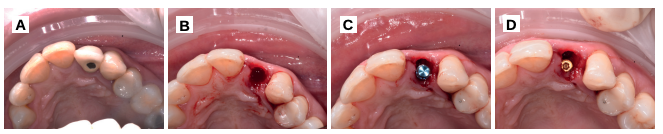

Tras 3 meses de la colocación del implante, se realizó la segunda fase, mediante una incisión horizontal palatinizada, para desplazar el tejido en una dirección vestibular (Figura 10). Se pudo apreciar el aspecto homogéneo del injerto de dentina, en contacto con el pilar de titanio (Figura 11), que fue rebasado con acrílico para la colocación de una corona provisional (Figuras 11 y 12). A la semana de la segunda fase, se valoró el aspecto del tejido gingival y la óptima ganancia de tejido a nivel horizontal (Figura 13).

de titanio para rebasar y confección de corona de resina

provisional (B-D).